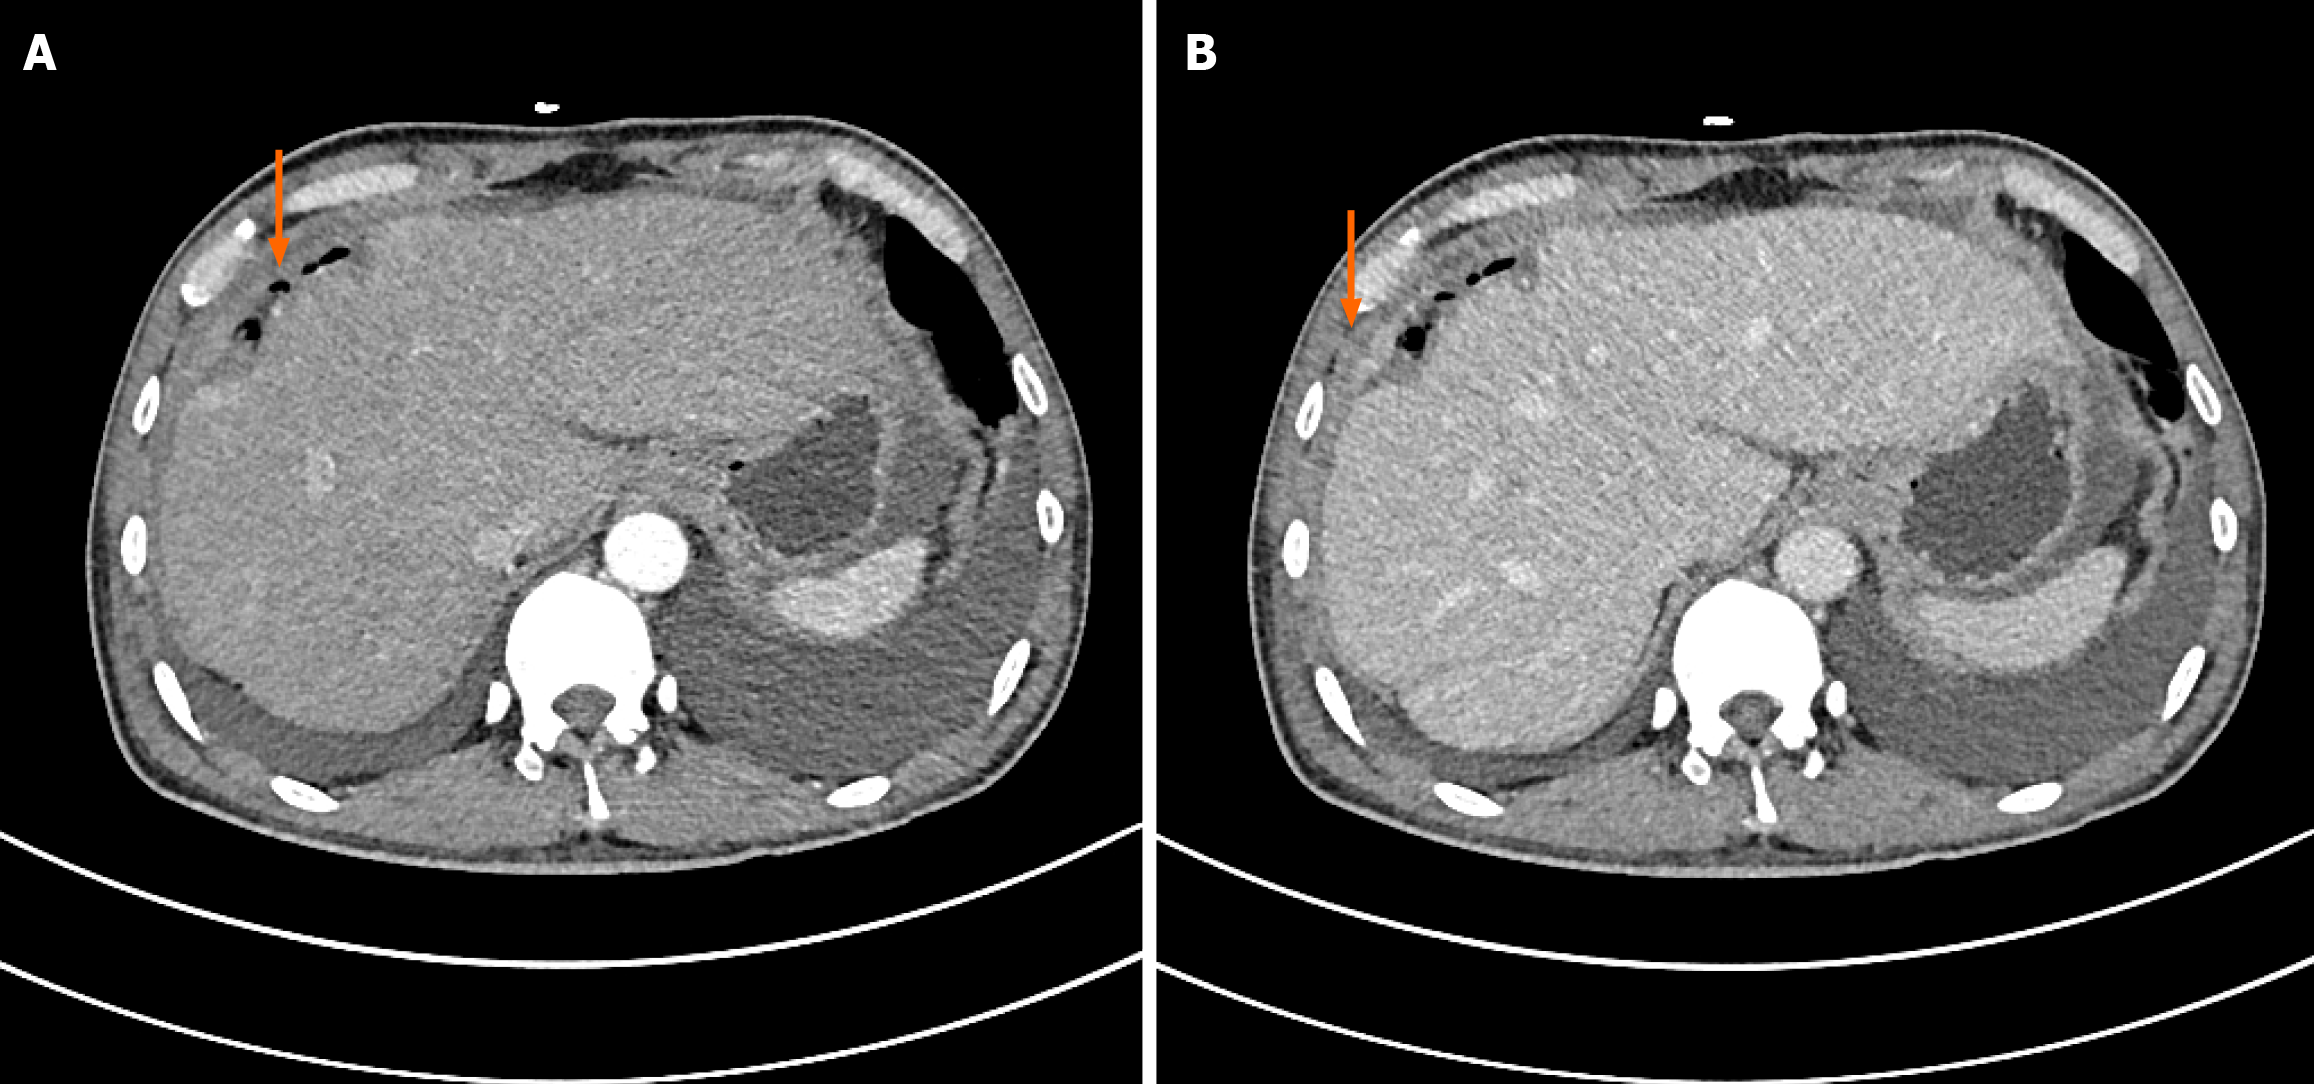

Abdominal enhanced computed tomography (CT) showed that the medial segment of the left lobe of the liver was clumpy with a slightly low density shadow, an unclear boundary with the surrounding area, uneven internal density, the lesion was approximately 6.4 cm × 3.7 cm in size with a thick wall, uneven continuous circular medium enhancement on the enhanced scan, and a nodular enhancement shadow in the arterial phase. A small amount of perihepatic effusion and slight thickening of adjacent peritoneum were observed (Figure 1). The middle hepatic veins and major hepatic arteries were not invaded by the tumor.